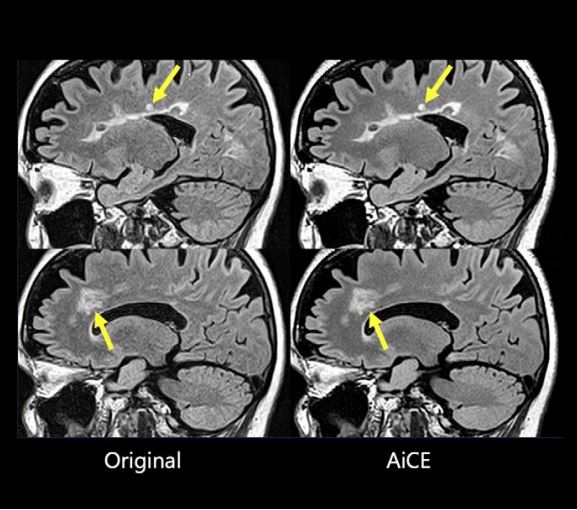

На рис. 1 показано, що AiCE навчено лише видаляти шум, зберігаючи анатомічні структури. На рис. 2 і 3 показано, що на реконструйованих AiCE зображеннях зберігаються анатомічні та патологічні особливості.

Рис. 3. Ураження розсіяного склерозу (стрілки) збереглися на зображенні, обробленому за допомогою AiCE.